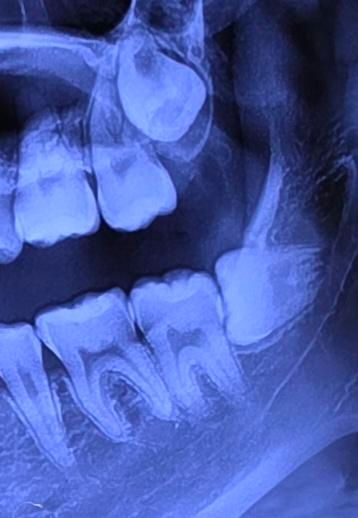

윗 사랑니가 둘 다 너무 이빨 라인보다 훨씬 위쪽에 위치해있는데 옆 어금니들을 이미 밀고 있는 상태인가요?

• 2번 째 사진

파노라마 사진은 입체를 2d로 표현하기 때문에 다양한 중첩과 왜곡이 발생합니다

2) 사랑니 맹출력은 20대 초반이면 거의 끝납니다

찾기는 보이는 부분이 음영으로 보이는 것은 충치가 있어서 그럴 수도 있지만 이 자리에 충치를 치료한 재료가 방사선 투과성이 있어서 보이는 것일 수도 있습니다.

정확한 확인을 위해서는 유관상으로 확인을 하는 것이 좋을 거라 생각합니다.

자세한 확인을 위해서 병원에서 진료를 받아보는 것을 권유드립니다.